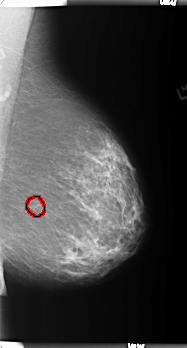

FILE: B_3367_1.LEFT_MLO.OVERLAY

TOTAL_ABNORMALITIES 1

ABNORMALITY 1

LESION_TYPE CALCIFICATION TYPE PLEOMORPHIC DISTRIBUTION CLUSTERED

ASSESSMENT 4

SUBTLETY 4

PATHOLOGY BENIGN

TOTAL_OUTLINES 1

BOUNDARY

LEFT_MLO LINES 5904 PIXELS_PER_LINE 3168 BITS_PER_PIXEL 12 RESOLUTION 50 OVERLAY